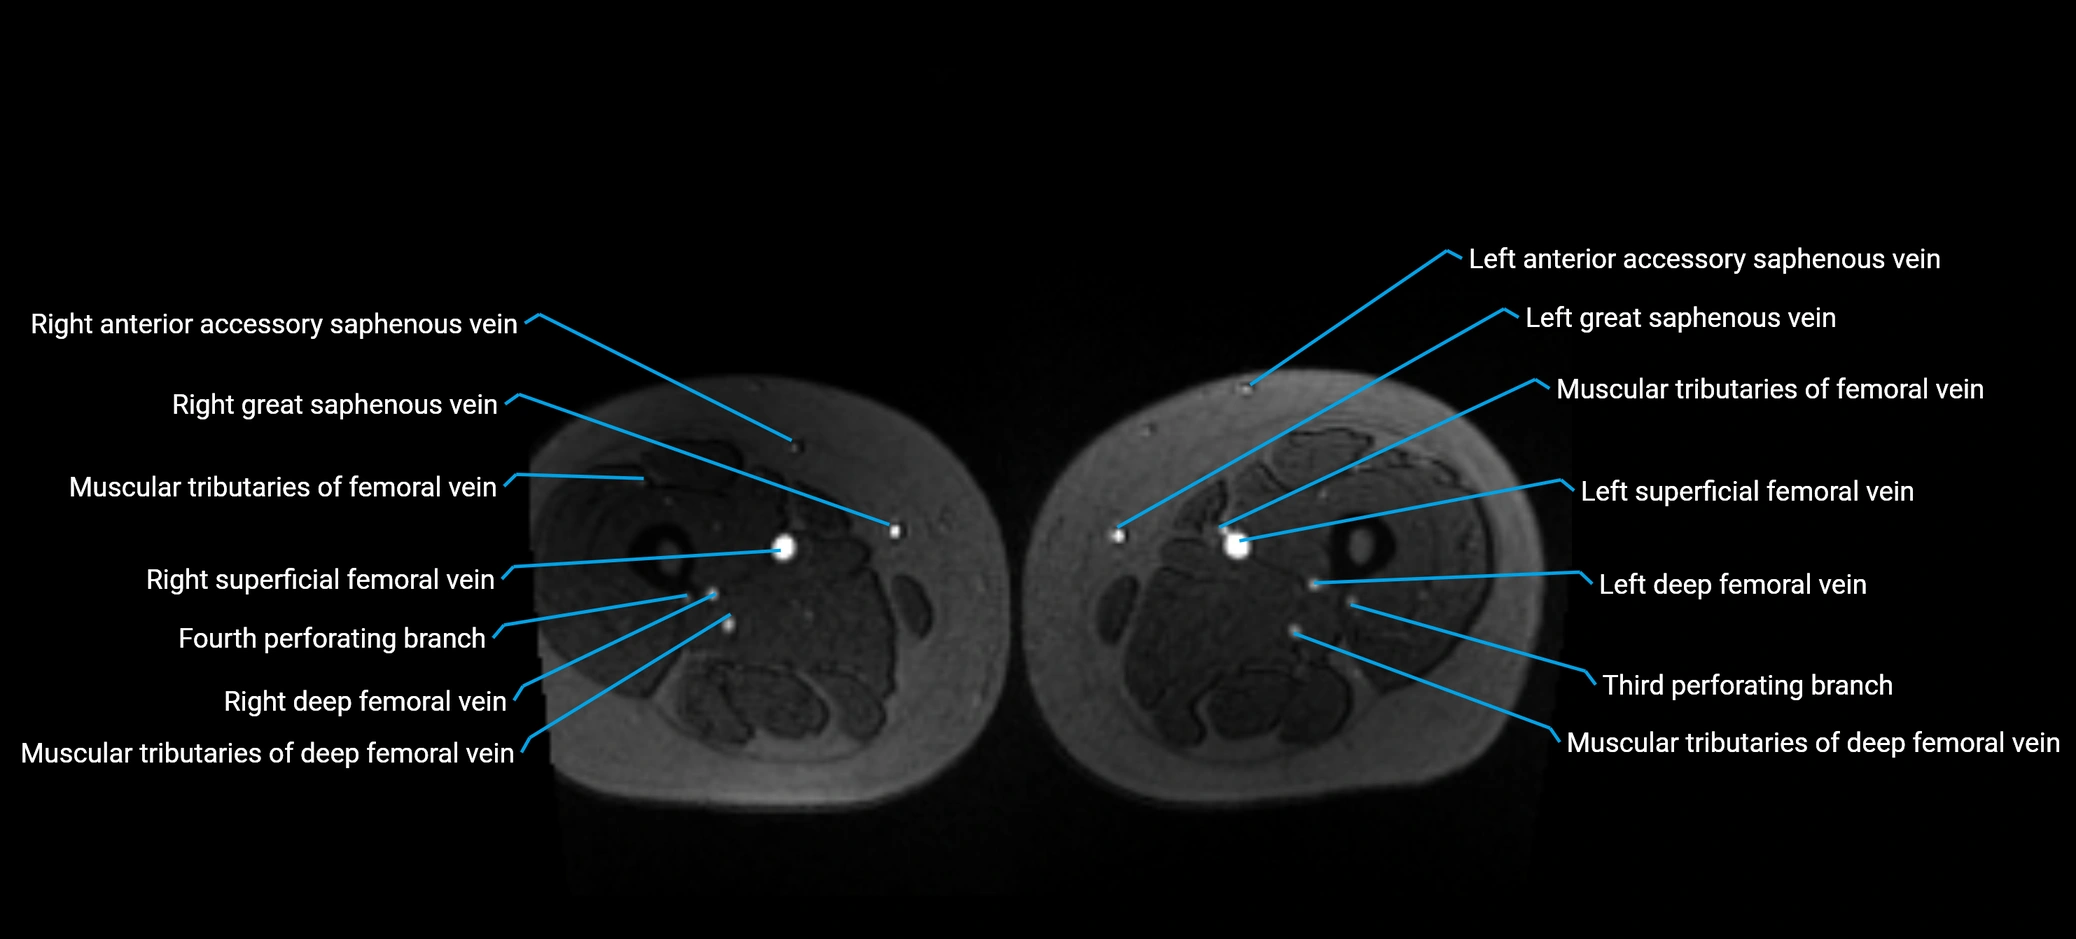

image